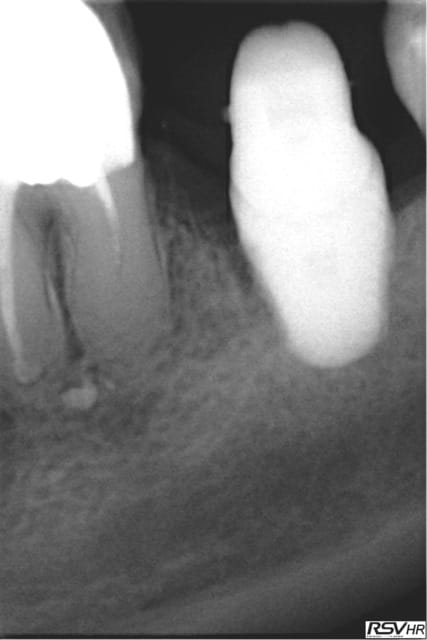

Les délires continuent !(clin d’œil doc Marcus)

37 fêlure-fracture au niveau du plancher en cours de RTE(1er radio avant RTE)

extraction dans la séance forage entre les racines extraction des racines re- forage après dans le septum

pose implant 7 mm long10mm le 11.06.2012

le 25.09.2012 pose d'un faux moignon titane transvissé et

couronne provisoire

RTE en cours sur 36

CCM définitives après

CBCT en 2014 OK pour l'implant